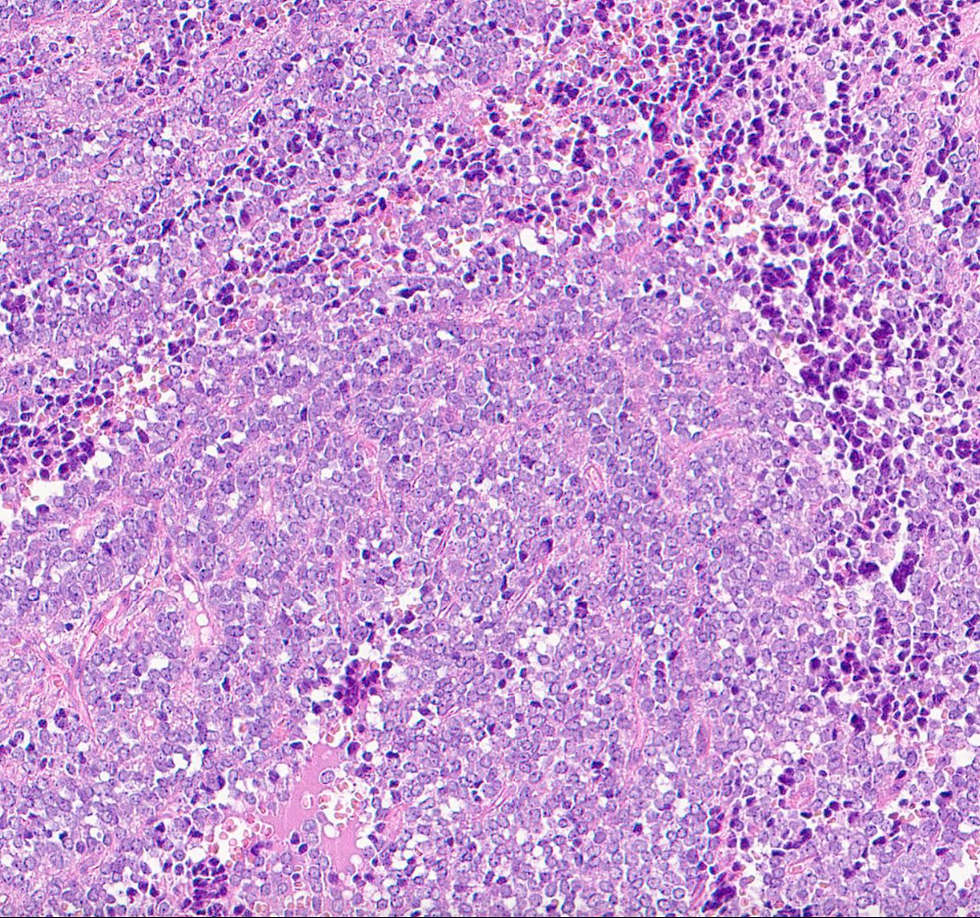

A 78-year-old male with a cervical lesion.

If the tumor is positive for CD99, what's the diagnosis?

This is a case of Ewing sarcoma. NKX 2.2 is the best sensitive and specific marker for Ewing sarcoma.

Monotonous small round blue cells arranged in sheets or solid aggregates.

Fibrous septa separating tumor cells.

Focal rosettes may be present.

Round nuclei, coarse chromatin, small nucleoli.

Cytoplasm ranges from scant to abundant and may be eosinophilic or clear.

Brisk mitotic activity.

Common necrosis.